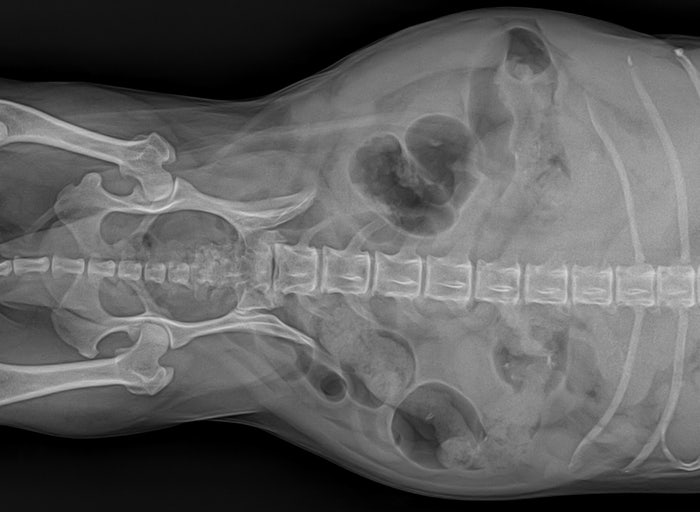

간에서 2개의 종괴가, 관찰 간에서 2개의 종괴가 관찰되었습니다.1. 좌횡격막에 가까운 위치(좌외엽 또는 내엽으로 추정)와 2. 위에 가까운 위치(좌외엽으로 추정)에 각각 1개씩 관찰되었습니다.

간종류의 크기 간종류의 크기는 1. 횡격막에 가까운 위치 약 2.17cm * 2.07cm * 2.06cm 2.위에서 가까운 위치 약 4.55cm * 3.25cm * 4.31cm 정도의 크기로 확인됩니다.위에 가까운 위치의 종괴는 소만곡과 매우 인접해 있어 유착 가능성도 배제할 수 없었습니다.반려동물의 간종양은 어디에 발생할까.이렇게 간은 여러 개의 잎으로 나뉘어져 있는데 이 여러 개의 간엽 중 어디에나 종양이 발생할 수 있습니다.얘는 두 군데서 발생했어요.애견간종양 치료방법→수술

간 종양이 확인되어 큰 간 종양을 제거해 주었습니다.